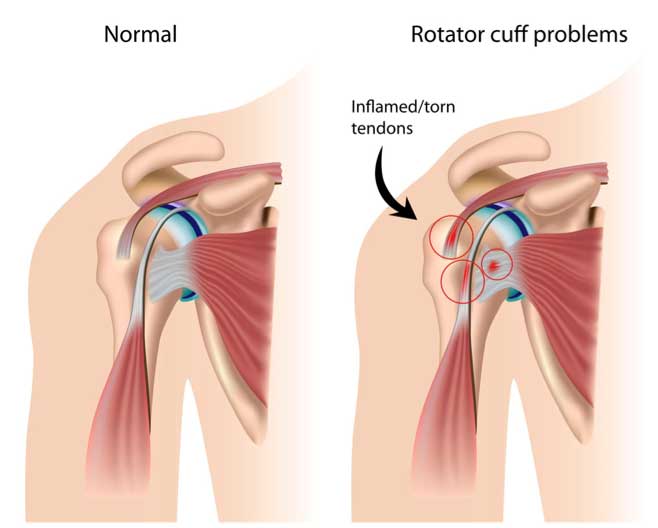

Introduction The rotator cuff, a group of muscles and tendons that stabilize the shoulder, is crucial for shoulder movement. When these tendons are torn, either due to injury or degeneration,…